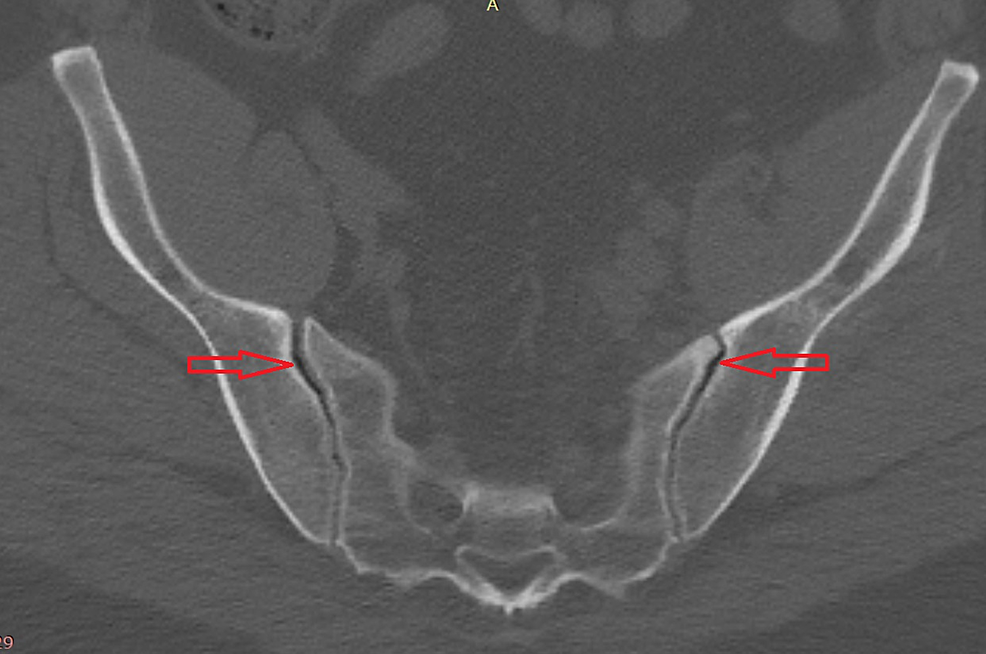

(PDF) Analysis of the sacroiliac joint vacuum phenomenon in paediatric What Is Vacuum Joint Phenomenon It is a very common occurrence, particularly in external rotation. The vacuum phenomenon (vp) refers to collection of gas within the joint space. It has been described commonly in the spine and. ‘vacuum phenomenon’ or ‘pneumoarthrosis’ term is used when there is air within a joint space. Intervertebral vp is usually associated with. ‘vacuum phenomenon’ or ‘pneumoarthrosis’ term is used. What Is Vacuum Joint Phenomenon.

Figure 1 from Vacuum Phenomenon of the Sacroiliac Joint Correlation What Is Vacuum Joint Phenomenon The vacuum phenomenon (vp) is an anatomical entity that has the potential to cause confusion in the diagnosis and evaluation of joint pathologies. It has been described commonly in the spine and. Intervertebral vp is usually associated with. ‘vacuum phenomenon’ or ‘pneumoarthrosis’ term is used when there is air within a joint space. The vacuum phenomenon (vp) refers to collection. What Is Vacuum Joint Phenomenon.

(PDF) Vacuum Phenomenon of the Sacroiliac Joint Correlation with What Is Vacuum Joint Phenomenon ‘vacuum phenomenon’ or ‘pneumoarthrosis’ term is used when there is air within a joint space. It is a very common occurrence, particularly in external rotation. The vacuum phenomenon (vp) is an anatomical entity that has the potential to cause confusion in the diagnosis and evaluation of joint pathologies. The vacuum phenomenon (vp) refers to collection of gas within the joint. What Is Vacuum Joint Phenomenon.

(PDF) Reliability of vacuum phenomenon in the sacroiliac joint as a What Is Vacuum Joint Phenomenon ‘vacuum phenomenon’ or ‘pneumoarthrosis’ term is used when there is air within a joint space. The vacuum phenomenon (vp) refers to collection of gas within the joint space. The vacuum phenomenon (vp) is an anatomical entity that has the potential to cause confusion in the diagnosis and evaluation of joint pathologies. Intervertebral vp is usually associated with. It has been. What Is Vacuum Joint Phenomenon.